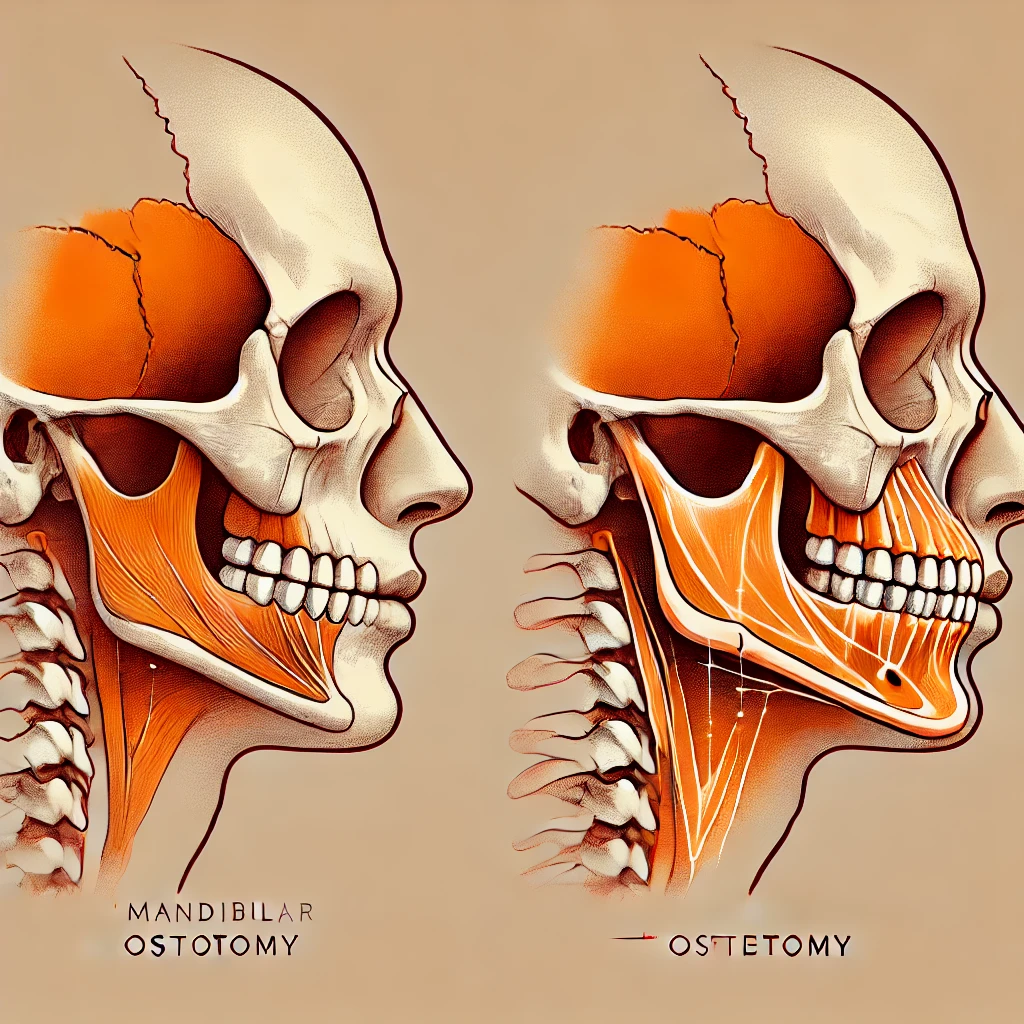

Nous vous présentons un cas de Génioplastie en Chin-Wing, une technique innovante d’ostéotomie du menton qui permet de repositionner à la fois le menton et les angles mandibulaires grâce à un mouvement de “tiroir”. Cette approche, souvent appelée Génioplastie 2.0, permet d’obtenir des résultats spectaculaires.

A la différence d’une simple génioplastie, cette technique chirurgicale plus invasive s’étend jusqu’aux angles mandibulaires.

•Les angles mandibulaires peuvent être abaissés tout en avançant le menton.

•Le mouvement s’effectue dans un plan vertical et horizontal, offrant une amélioration globale du profil du patient.